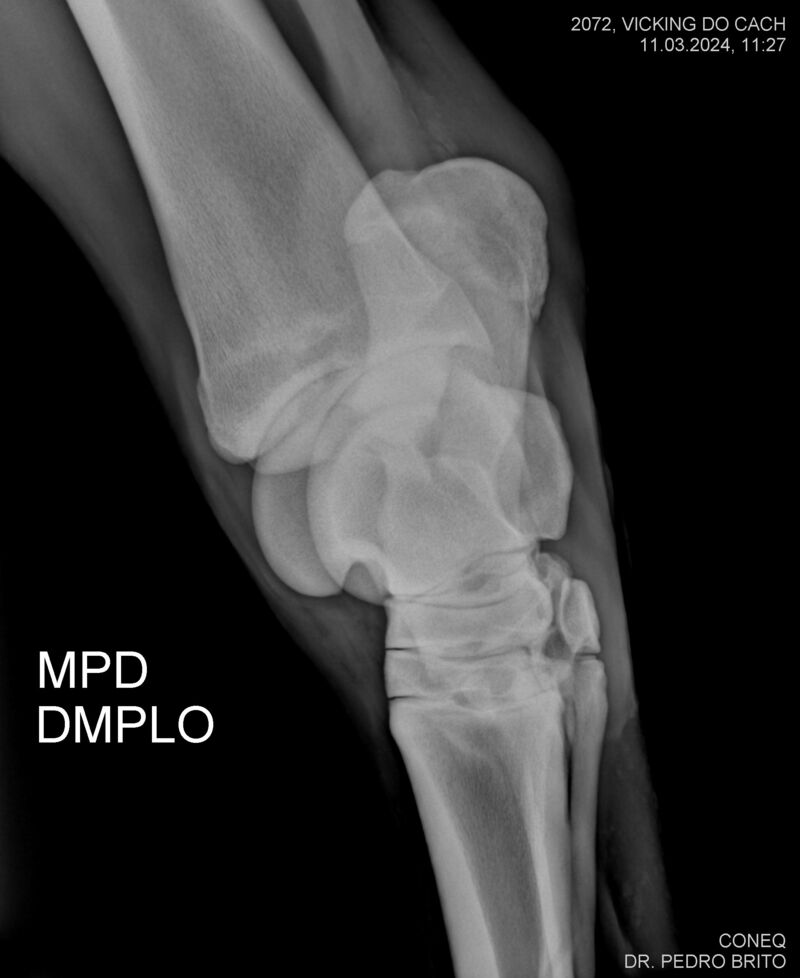

VIKING DO CACH